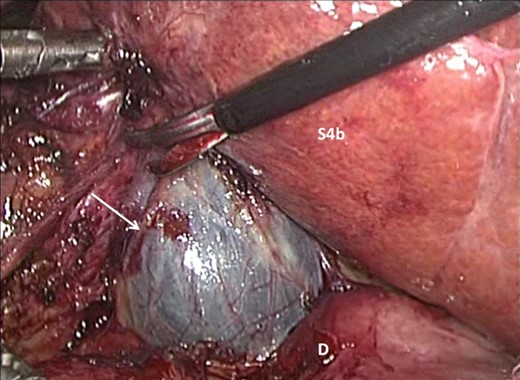

Careful dissection with ‘hot scissors’ has presented the ‘fundus’ of the gallbladder remnant (arrow). The duodenum (D) and segment IVb of the liver (s4b) are visible after dissection.